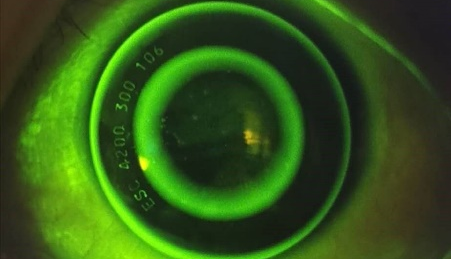

通过裂隙灯检查,能帮助我们排除一些不适合戴OK镜的疾病,比如:活动性的角膜感染或者其他急慢性眼前节炎症、眼睑异常等。而通过荧光染色和裂隙灯的配合,不仅能了解眼睛是否存在干眼的问题,还能帮助观察镜片在眼睛上的中央定位、镜片活动度及松紧度等。

结合角膜地形图和荧光配适图,能帮助医生选择OK镜的试戴参数及进行试戴评估。